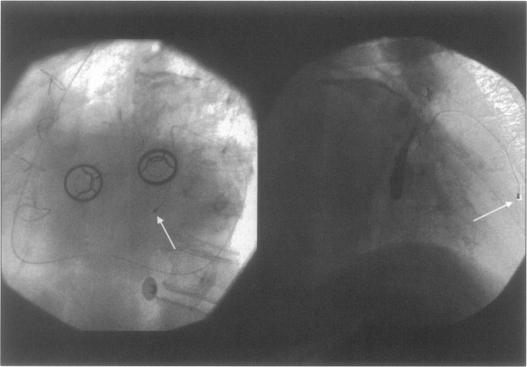

在一名有人工三尖瓣假体的患者中经静脉植入心室起搏导线。

Transvenous implantation of a ventricular pacing lead in a patient with an artificial tricuspid valve prosthesis.

The preference for treatment of symptomatic bradycardia is transvenous right ventricular pacing combined with atrial synchronisation if applicable. In the case of congenital anomalies where no conduit is present between the peripheral veins and the right ventricle, it is not possible to place the ventricular pacing lead in the right ventricle. Also the presence of an artificial valve in the tricuspid position excludes placement of an endocardial right ventricular pacing lead. Since the introduction of biventricular pacing, new guiding catheters and leads used as a transvenous route for left ventricular pacing are available. We report implantation of a ventricular pacing lead in the great cardiac vein for permanent ventricular pacing in a patient with a tricuspid valve prosthesis.

对于有症状的心动过缓,首选治疗方法是经静脉右心室起搏,如适用可联合心房同步起搏。对于外周静脉与右心室之间不存在导管的先天性异常情况,无法将心室起搏导线置于右心室内。此外,三尖瓣位置存在人工瓣膜也排除了心内膜右心室起搏导线的置入。自从双心室起搏引入以来,有了新的引导导管和用作左心室起搏经静脉途径的导线。我们报告了在一名有三尖瓣人工瓣膜的患者中,将心室起搏导线植入心大静脉以进行永久性心室起搏的情况。